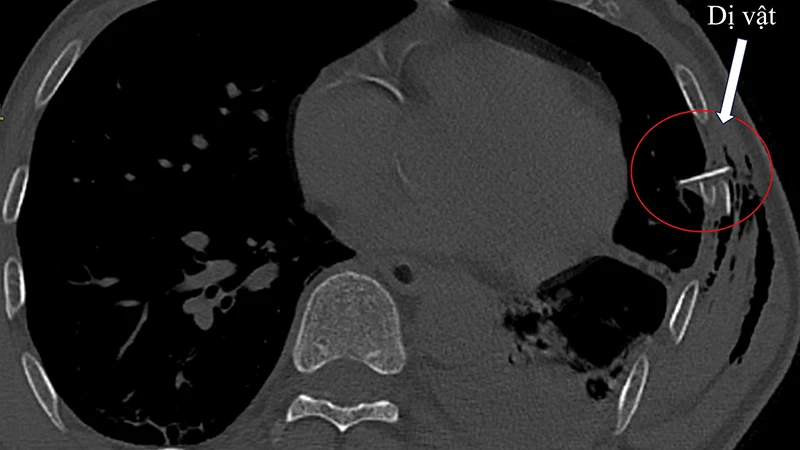

Sáng 1/4, Bệnh viện đa khoa Trung ương Quảng Nam cho biết, đơn vị vừa cứu sống một bệnh nhân nam (63 tuổi) bị tai nạn giao thông gây chấn thương thủng phổi do mảnh gãy của xương sườn đâm vào.

Chiều 28/12, Bác sĩ chuyên khoa 2, Nguyễn Tam Thăng, Phó Giám đốc Bệnh viện đa khoa Quảng Nam cho biết, bệnh viện vừa cứu sống một bệnh nhân mất máu nguy kịch do vết thương thấu ngực. Đây là bệnh nhân đầu tiên bị mất máu nguy kịch được cứu sống, sau 10 ngày tiếp nhận, phẫu thuật và điều trị.